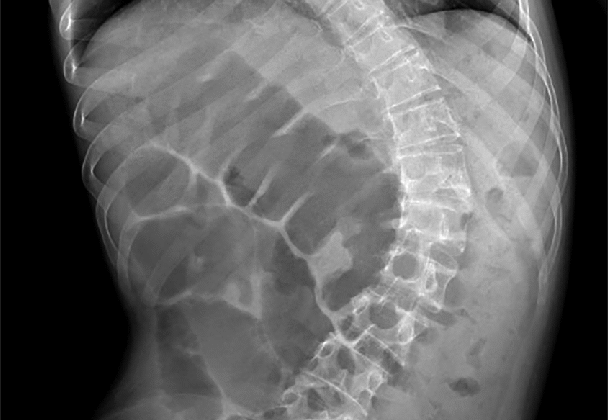

يعاني كثير من الأطفال والمراهقين وحتى الكبار من مشكلة اعوجاج العمود الفقري، وهي حالة طبية تؤدي إلى انحناء غير طبيعي في العمود الفقري. لكن هل تعلم أن هذا الانحناء قد لا يقتصر تأثيره على الظهر فقط؟ في الواقع، يمكن أن يؤثر بشكل مباشر على صحة الجهاز الهضمي ويسبب أعراضًا مثل الإمساك والانتفاخ واضطرابات في حركة الأمعاء. في هذا المقال، نُجيب على أهم الأسئلة التي تدور في أذهان المرضى وأهاليهم حول العلاقة بين اعوجاج العمود الفقري والجهاز الهضمي، ونقدم نصائح فعالة لتحسين جودة الحياة والهضم.

نعم، في بعض الحالات، قد يسبب اعوجاج العمود الفقري مشاكل في عملية الهضم، وأشهرها الإمساك المزمن. السبب وراء ذلك يعود إلى أن انحناء العمود الفقري قد يؤدي إلى:

تغيير موضع الأمعاء والمعدة داخل البطن، مما يؤثر على حركتها الطبيعية.

الضغط على الأعضاء الداخلية، خاصة في حالات الانحناء الشديد.

تأثير غير مباشر على الإشارات العصبية التي تتحكم في حركة الأمعاء.

هذه العوامل مجتمعة يمكن أن تُبطئ من حركة الأمعاء وتُسبب الإمساك والانتفاخ والشعور بعدم الراحة.